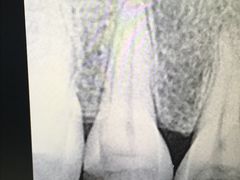

• 武汉大学人民医院(首义院区)

• -武汉大学人民医院(首义院区)

洲之珍珠快入锅 | 18-06-22

黎子_1831 | 18-06-17

请叫我官人 | 18-05-28

Q糯米糍 | 18-05-10

Q糯米糍 | 18-04-26

Q糯米糍 | 18-04-25